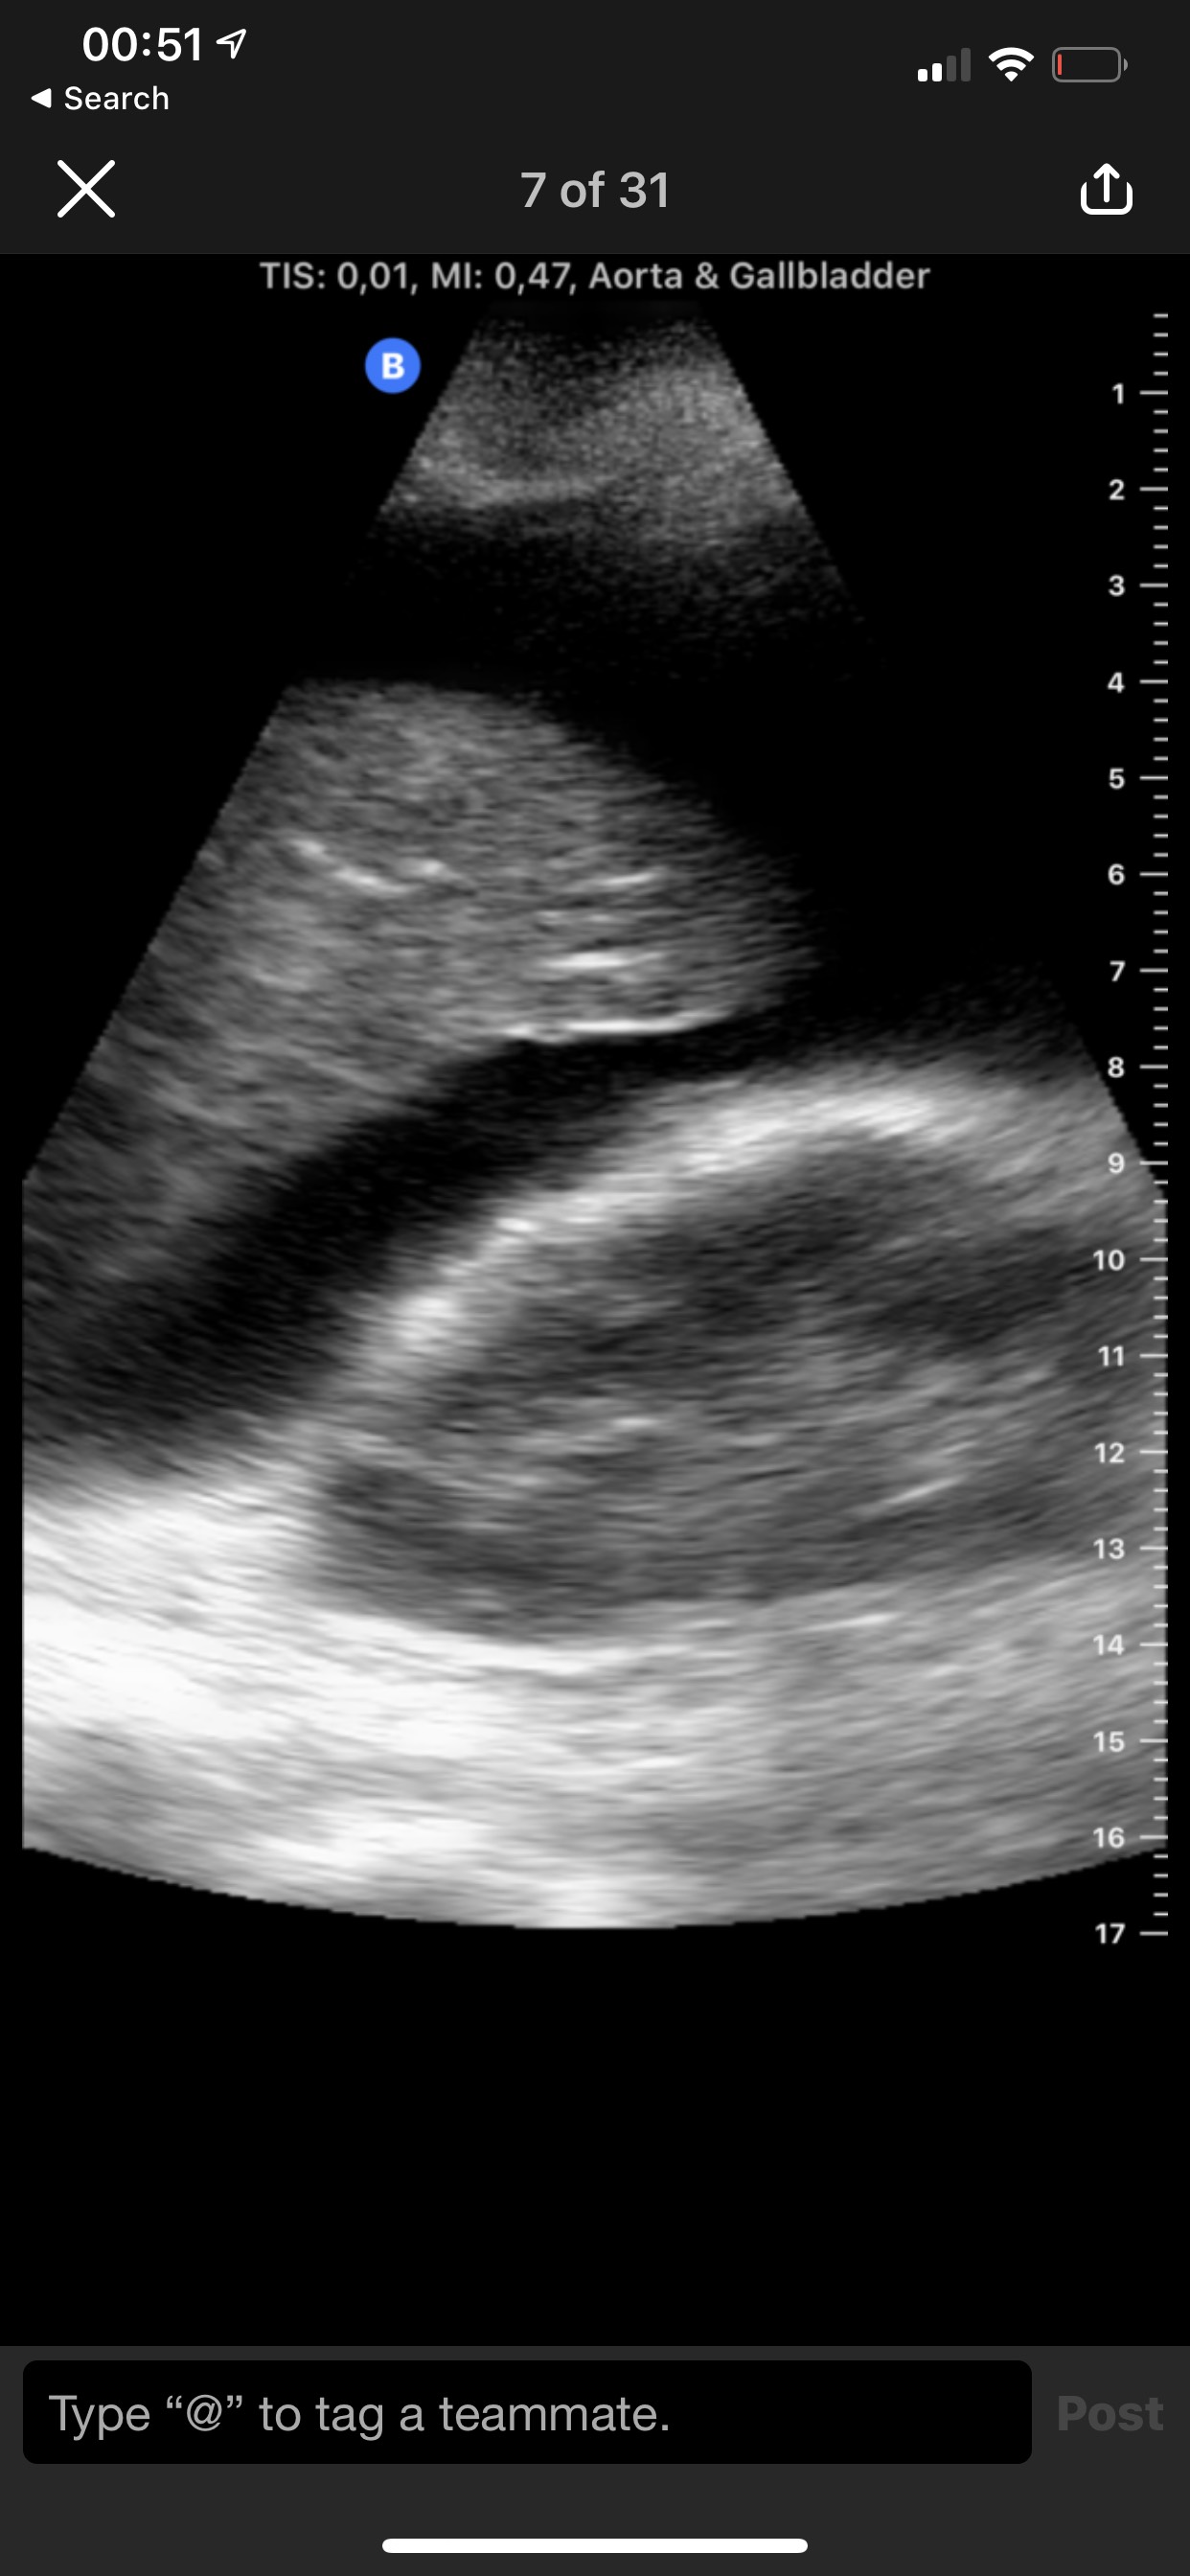

Eksempel på bilete frå Butterfly iQ. Massiv ascites hjå kreftpasient. Lever og høgre nyre. Samtykke til undervisingsbruk frå pasient.